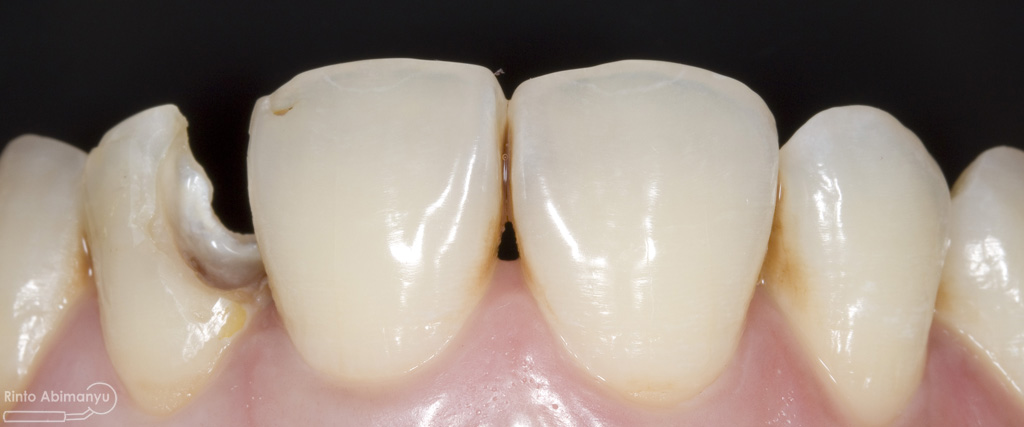

Pada pemeriksaan intra oral terlihat gigi 23 dan 24 mengalami karies dan cukup banyak sisa makanan terjebak disana…

Pemeriksaan respon dingin pun menunjukkan hasil negatif, untuk menambah data dalam penegakan diagnosis maka dilakukan pengambilan ronsen pada gigi2 tersebut

Terlihat dari ronsen tersebut karies pada gigi 23 24 sudah mencapai pulpa… dari informasi pemeriksaan klinis dan ronsen maka didiagnosis gigi tersebut nekrosis.. Saya jelaskan kepada pasien mengenai kondisi gigi2 nya dan rencana perawatan yang akan saya lakukan…